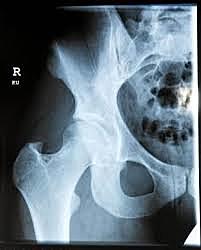

• Prótesis de wiles

Prótesis de wiles

Articulación metal – metal con un componente acetabular y otro femoral con un vástago corto en cuello femoral y fijado al fémur proximal con una placa.